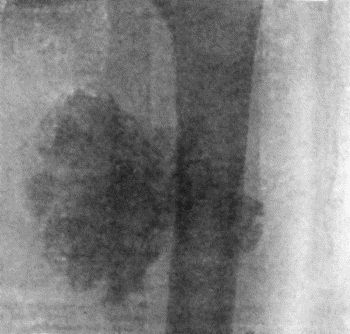

71.Radiogram of Aneurysm of Aorta 303

72.Sacculated Aneurysm of Abdominal Aorta 304